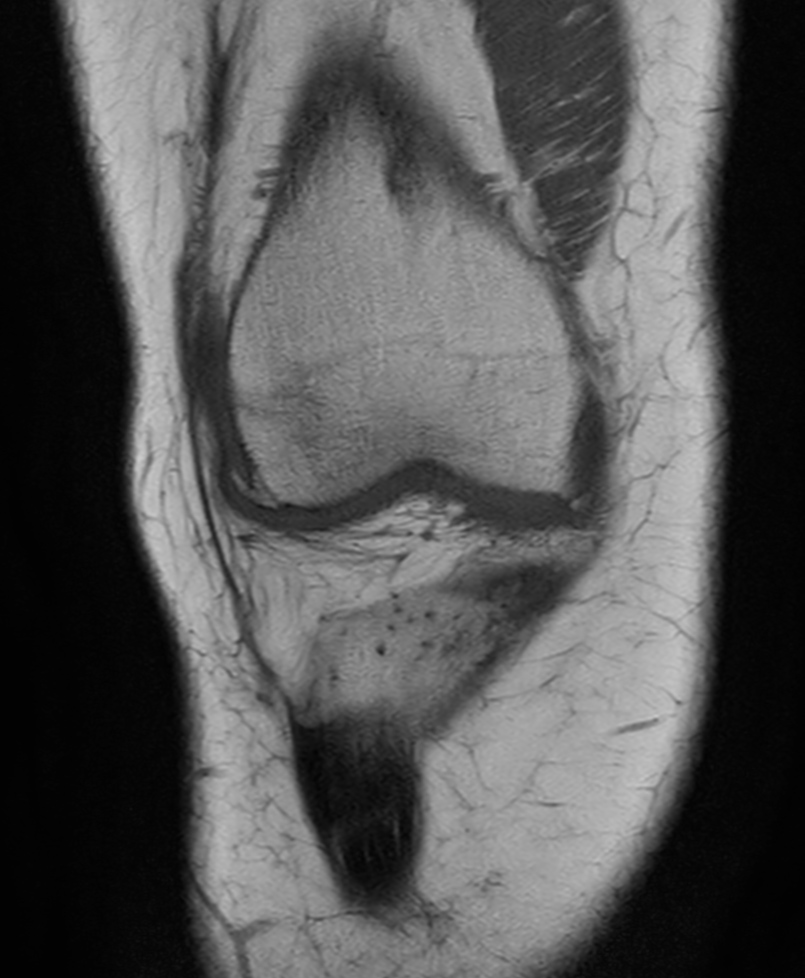

Coronal T1w TSE